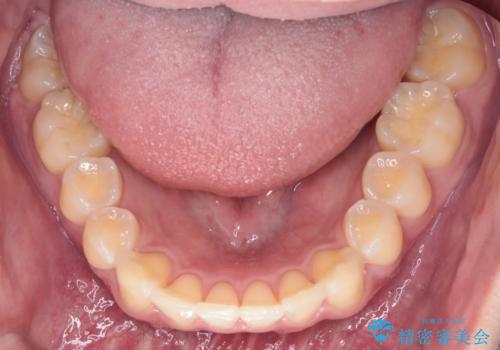

【インビザライン】短期間で出っ歯を治したい

- 出っ歯と口元の突出感が気になるということで来院されました。抜歯矯正も考えられますが、今回は早く終わらせたいという要望があり非抜歯での治療にしました。また遠方から来院されているため、来院回数のおさえられるインビザラインを選択しました。

非抜歯での治療のため、今回はスペース確保のために遠心移動とおもにIPRの処置を取り入れました。